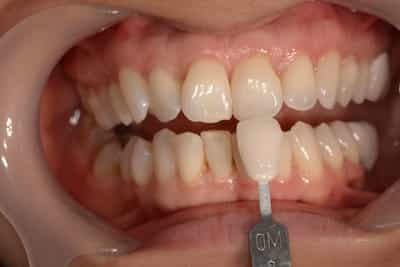

Cas numero 1 :

Etude du cas et proposition

Cas terminé